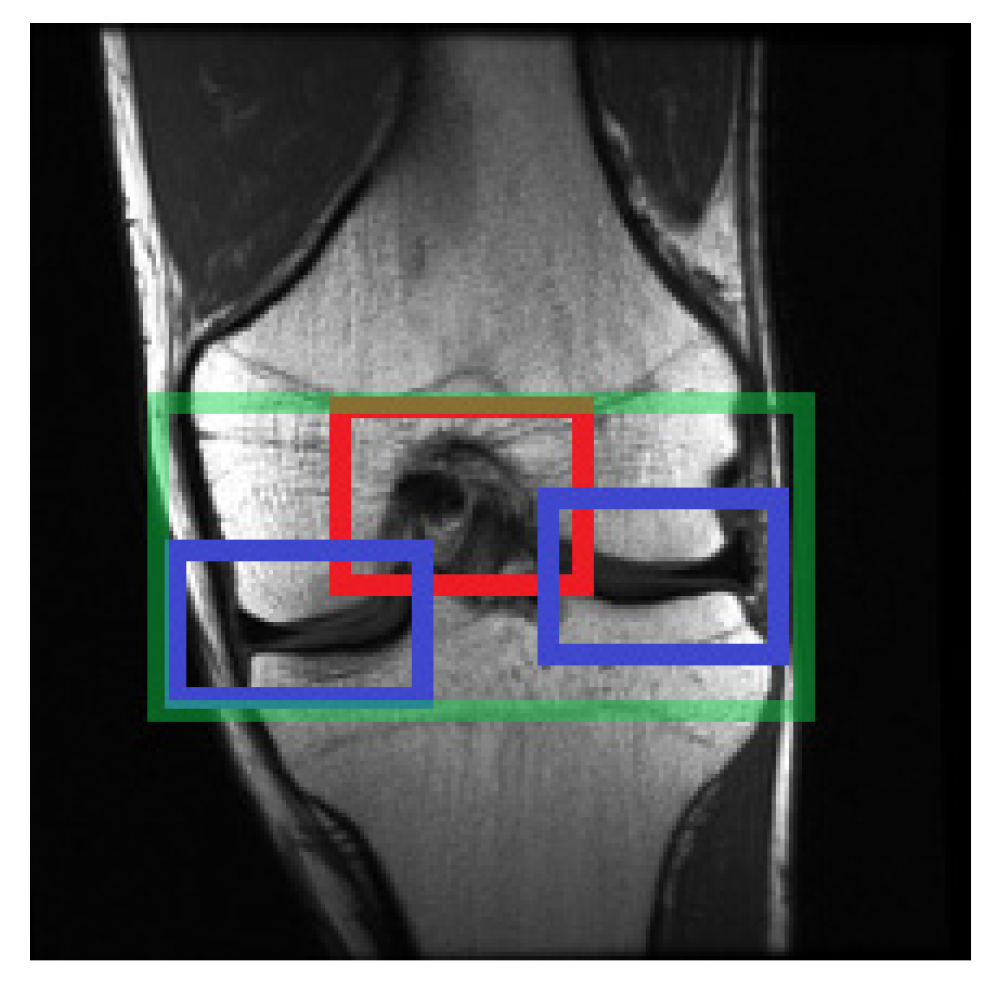

2.4. Selecting the Relevant Area

2.4.1. Selecting Relevant Areas on the Sagittal Axis

2.4.2. Selecting Relevant Regions on the Coronal Axis